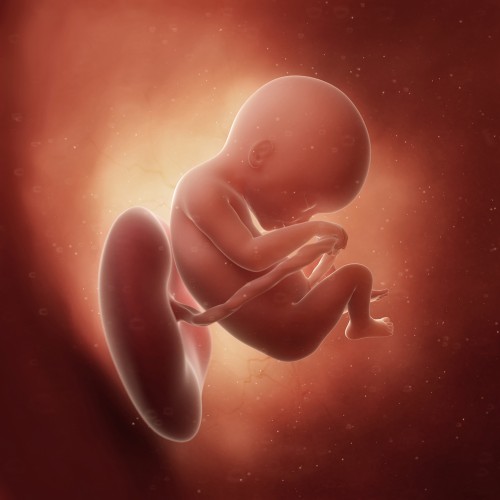

К концу восемнадцатой недели беременности размер плода достигает 12-14 см, а его масса увеличивается до 150 г. По своим габаритам он напоминает манго. Пропорции тела становятся более гармоничными, продолжается окостенение скелета, а фаланги пальцев рук и ног завершают формирование. На подушечках пальцев уже проявляется уникальный рисунок.

Как выглядит плод на 18 неделе беременности?

Его вес сейчас составляет 150 г, а длина – около 12-14 см. Малыш постоянно копошится, и ты, возможно, уже достаточно часто ощущаешь это. Сосудики, по которым течет кровь, отчетливо видны сквозь тонкую кожу, поэтому кожа выглядит ярко-красного цвета. Ушки заняли окончательную позицию и даже немного оттопырились.